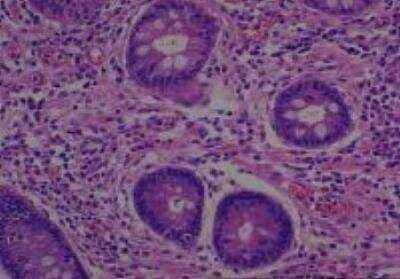

Scientific Data Images for Human Multi Tissue MicroArray (Normal Adjacent)